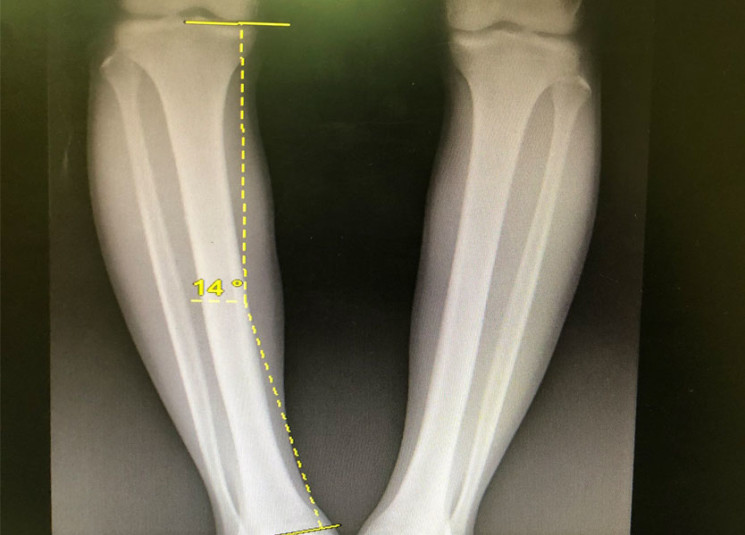

مرض تقوّس الساقين تشوّه جسدي في الساقين يتميّز ببعد الركبتين عند الوقوف ووضع القدمين بمحاذاة بعضهما البعض، وهو مرض معروف ومنتشر عند العديد من الأطفال، ويظهر بشكل أكثر عندما يبدأ الطفل بالمشي، فتظهر الساقان متقوّستين، والركبتان مبتعدتين عن بعضهما البعض.

ثمة نوعيان لتقوس الساقين. فبحسب د. بشير غسطين، أخصائي في جراحة العظم والمفاصل والطب الرياضي الجراحي، «يصيب النوع الأول منطقة تحت الركبة أي الـtibia، فيما يعرَف النوع الآخر بـ Pied bot. إنَّ مرض التقوس خلقي بأنواعه، وهو يظهر مباشرة بعد الولادة. وثمة عامل وراثي ولكنّ الطابع الخلقي طاغٍ. إذاً إن كان يعاني أحد الوالدين من تقوس الساقين، لا يعني بالضرورة أنَّ الولد سيعاني من هذا المرض، إلّا إذا كان التقوس جزءاً من متلازمة ما مثل الجنف (سكوليوز)، أو من تشوّهات خلقية كعظمة ناقصة... هنا يكون السبب الرئيسي عادةً وراثياًّ».

معظم حالات تقوّس الساقين طبيعية إلى عمر السنتين، ولا حاجة للقلق منها. وثمة درجات مختلفة من هذا المرض. وعندما يكون التقوس جزءاً من متلازمة، تكون درجة التقوس متقدمة. كما تزداد درجة التقوس مع العمر، لذلك يجب الكشف عن هذا المرض في عمر مبكر وعلاجه. يفسّر د. بشير أنّه «من الضروري علاج التقوس تحت الركبة، أي الذهاب لدى أخصائي أطفال، والقيام بجلسات متكررة لتصويب الساقين وتفادي الحاجة إلى عملية. وإن لم يتحسّن الوضع بالعلاج أو لم يخضع المريض إلى علاج في الأساس، سيحتاج إلى عملية جراحية. وتخلّف هذه العملية آثاراً جانبية على المريض حتى بعد مرور السنين، لذا من الأفضل تفاديها. أما في حالات الـpied bot، فيعاني غالبية المصابين من تقوس على شكل قوسين ( ) أي إلى الداخل، وهذا أمر طبيعي. ويجب تطمين الأهل في هذه الحالة، فهذا النوع من التقوس يختفي مع المشي والتقدم في العمر. أما إذا كان التقوس إلى الداخل أو إلى الخلف، فيكون تشوّهاً خلقيّاً وعلينا البحث عن مشكلات مرتبطة بهذا التقوس».